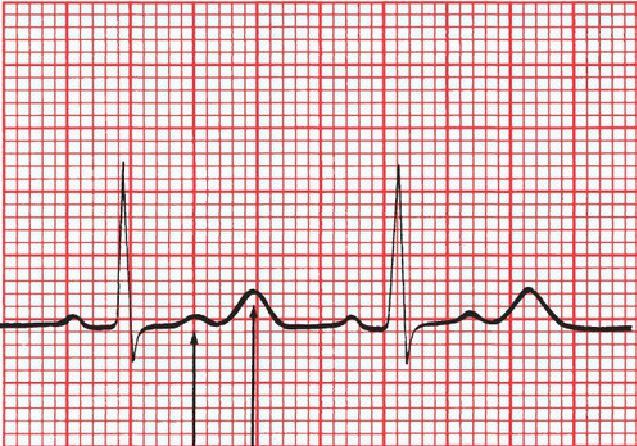

What kind of electrolyte disturbance produces this ECG?

Hypokalemia. The U waves are even more prominent than the T waves.